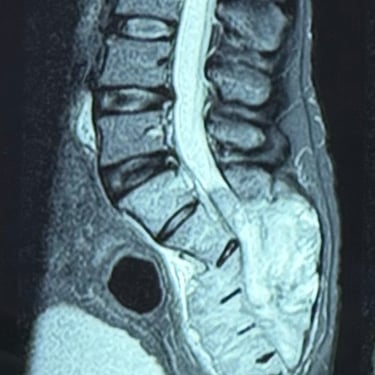

Sarcoma Sacro: Citorreducción Tumoral y Descompresión Nerviosa

El sarcoma sacro es una neoplasia poco frecuente y de manejo complejo que puede generar dolor severo, alteraciones neurológicas y compromiso de la movilidad por afectación de las raíces nerviosas sacras. El tratamiento quirúrgico mediante citorreducción tumoral tiene como objetivo disminuir el volumen del tumor, mientras que la descompresión nerviosa permite aliviar la presión sobre las estructuras neurológicas comprometidas. Este abordaje busca mejorar el control del dolor, preservar la función neurológica y optimizar la calidad de vida del paciente. La planificación cuidadosa y el manejo multidisciplinario son fundamentales para obtener mejores resultados clínicos.